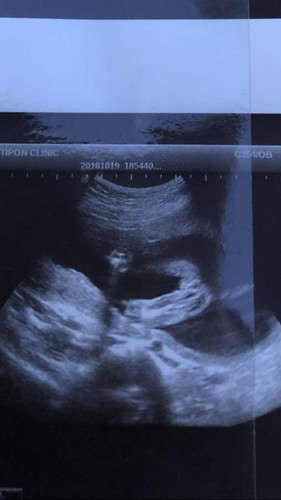

อยากสอบถามคุนแม่ว่าเพศ ญ / ช ค่ะ ดูออกไหมค่ะ ไปซาวได้5เดือน 3 วันค่ะ

น้อง ผู้หญิง หรือ ผู้ชายค่ะ

อันนี้แม่ๆดูออกกันไหมคะว่า ญ/ช โดยส่วนตัวมองไม่ออกค่ะ😅😅 ซาววันนี้เลยหมอบอกเพศช เน้นจู๋ให้เลยหมอซาวให้เน้นๆเลยค่ะ

ดูไม่ออกเลยค่ะ ว่าหมอซาวด์ส่วนไหนของน้องมา ครั้งหน้าแม่แจ้งหมอเลยค่ะ ให้แคปรูปตรงหว่างขาน้องมาเลย

ในรูปก็หว่างขาน้องนะคะ ดูดีๆค่ะแม่ ดูจากรูปน่าจะผู้หญิง ค่ะ

ญ.จ้าแม่ ไม่เห็นไข่กะไอ้จู๋เลย

ผญ ค่ะ ซาวตอน5 เดือนพอดีค่ะ

หมอว่า ผู้หญิง 90% นี้ซาวตอน5เดือนค่ะ